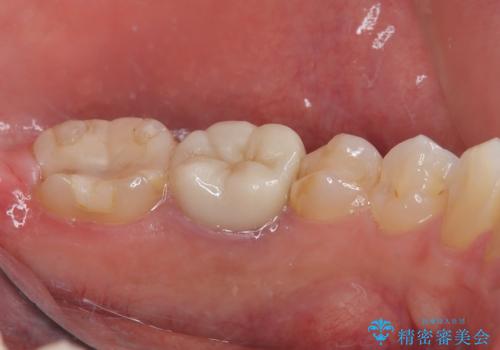

拡大鏡視野下で詰め物、虫歯を除去しフルジルコニアクラウンに適切な形に整えました。

型どりの際には唾液も多く舌も動いてくるため個歯トレーにて精密印象を行っています。

仮歯に変える前に左下の埋伏親知らず抜歯を行っています。